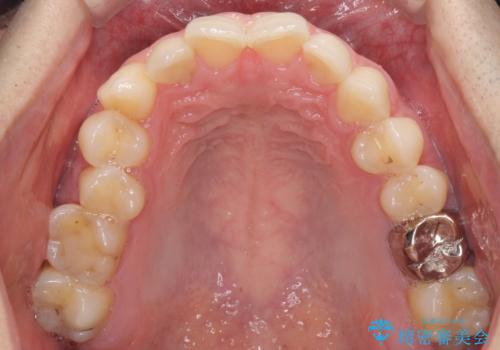

ディープバイトと叢生 インビザラインによる矯正治療

- 前歯のディープバイトと叢生を気にして来院された患者様です。

上下ともに叢生が認められたため、親知らずすべてを抜歯し、歯列全体を後方へ移動させることで歯列を整えることとしました。

上顎奥歯の銀歯も気になっていたので、矯正治療の途中でセラミッククラウンへ変更し、その後歯列を仕上げていくこととしました。

ディープバイトもデコボコも改善され、気になっていた銀歯もセラミックとなり、患者様には大変満足していただきました。